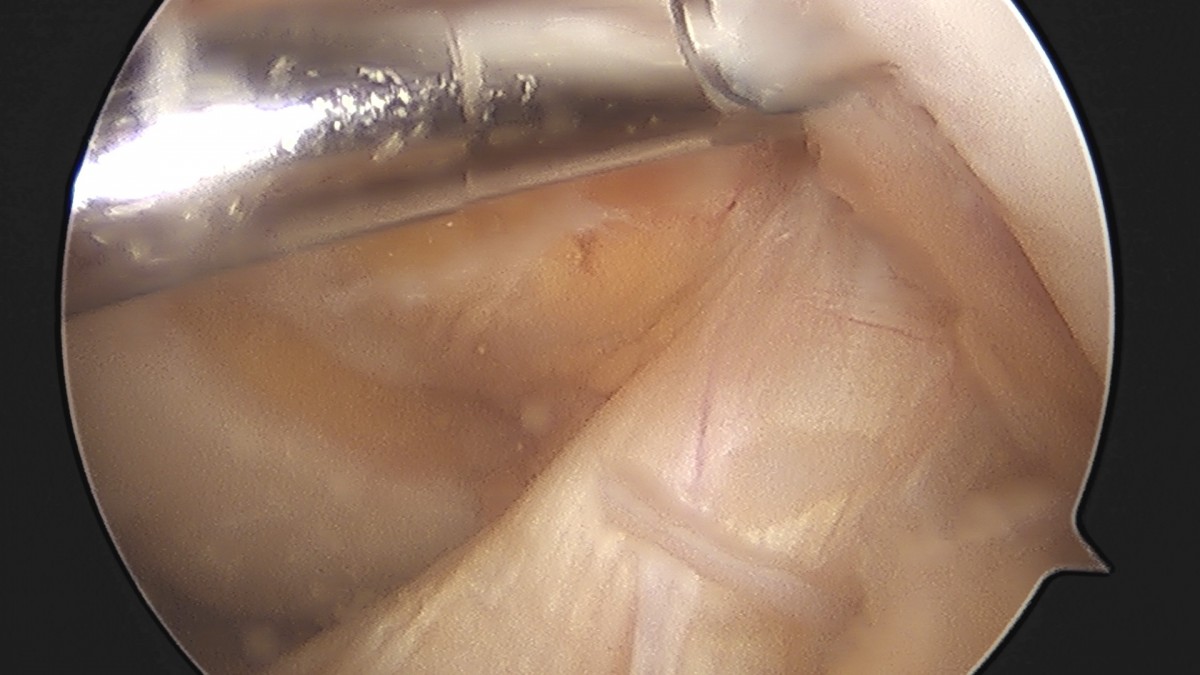

이재상원장님 무릎 반월상 연골판 절제술 박상O 환자

dae765e4d9ac96aee867c9d6292d8784_1758006443_5955.jpg